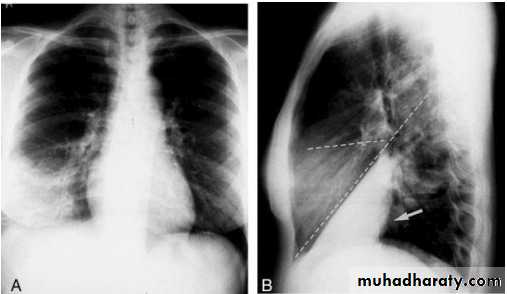

Pleural Effusion on Chest Radiographs.

Posteroanterior (A) and lateral (B) chest radiographs demonstrate the typical meniscoid appearance (arrows) in a patient with a left pleural effusionHydropneumothorax.

When fluid and air are present in the pleural space on an upright chest x-ray, a perfectly straight horizontal line will extend all the way from the spine to the edge of the pleural cavity. In this patient, a loculated right basilar hydropneumothorax is present.The air/fluid interface is easily seen (arrows). If this were a lung abscess, the air/fluid level would be very unlikely to extend all the way from the medial to the lateral aspect of the hemithorax.